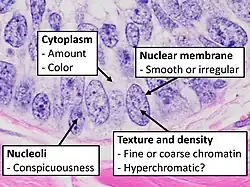

Subcellular features (may need highest magnification)

Subcellular features (may need highest magnification)